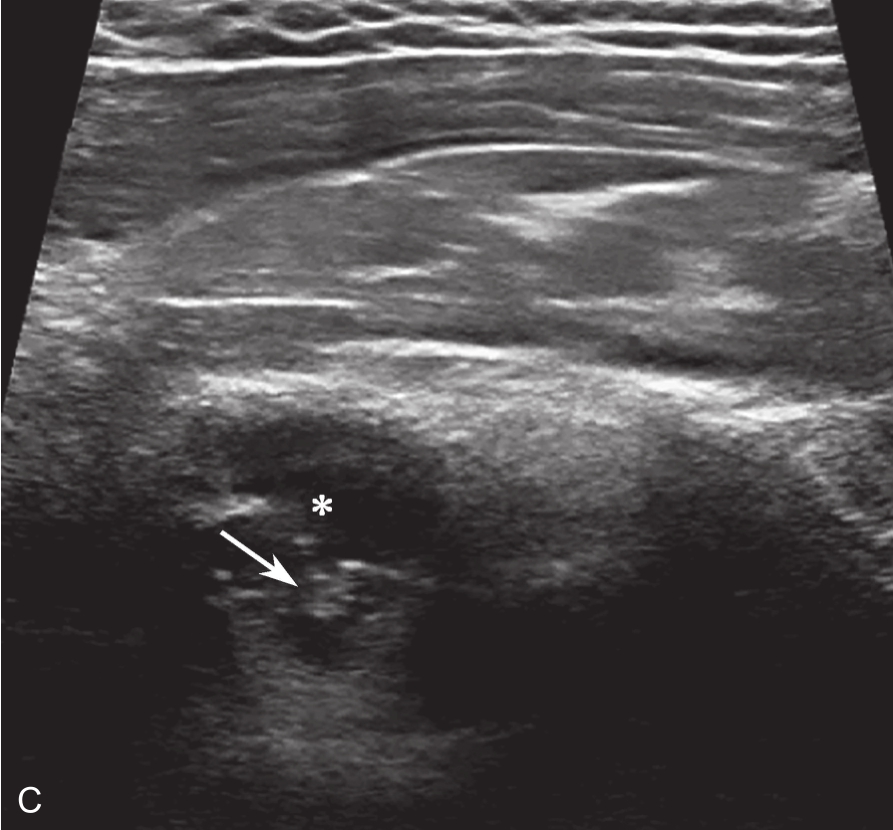

▲ 图 2-6-4(续)

C.超声引导下类固醇及生理盐水注射;D.注射治疗后关节腔扩张;双星号:增厚关节囊;箭头:穿刺针;单星号:关节腔